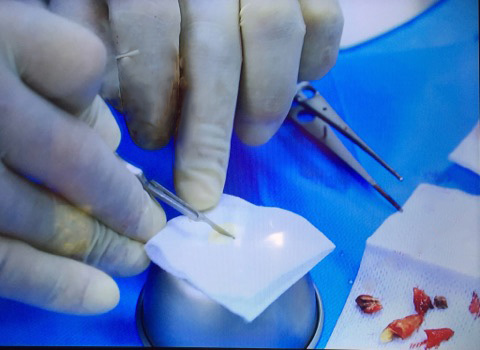

Мастер-класс начался с обсуждения предстоящей операции и снимка компьютерной томографии, после чего участники смогли присутствовать на операции.